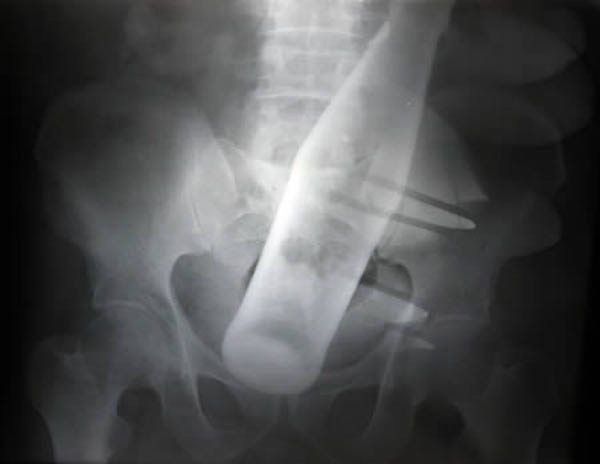

12 / 15Butelka

Musiał być bardzo spragniony.